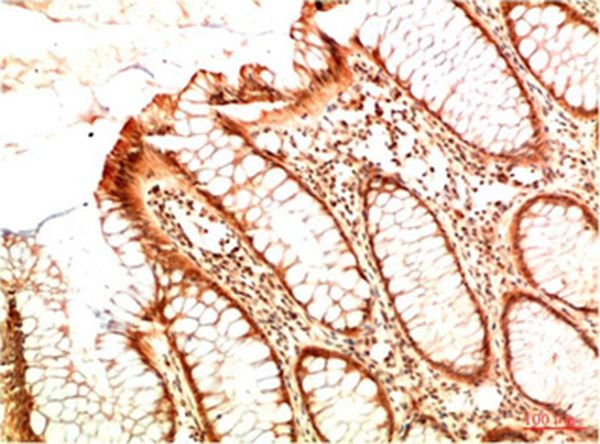

1. Immunohistochemical analysis of paraffin-embedded Human Breast Carcinoma Tissue using Acetyl P53(K382) Mouse mAb diluted at 1:200.

2. Immunohistochemical analysis of paraffin-embedded Human Colon Carcinoma Tissue using Acetyl P53(K382) Mouse mAb diluted at 1:200.

3. Immunohistochemical analysis of paraffin-embedded Human Colon Carcinoma Tissue using Acetyl P53(K382) Mouse mAb diluted at 1:200.